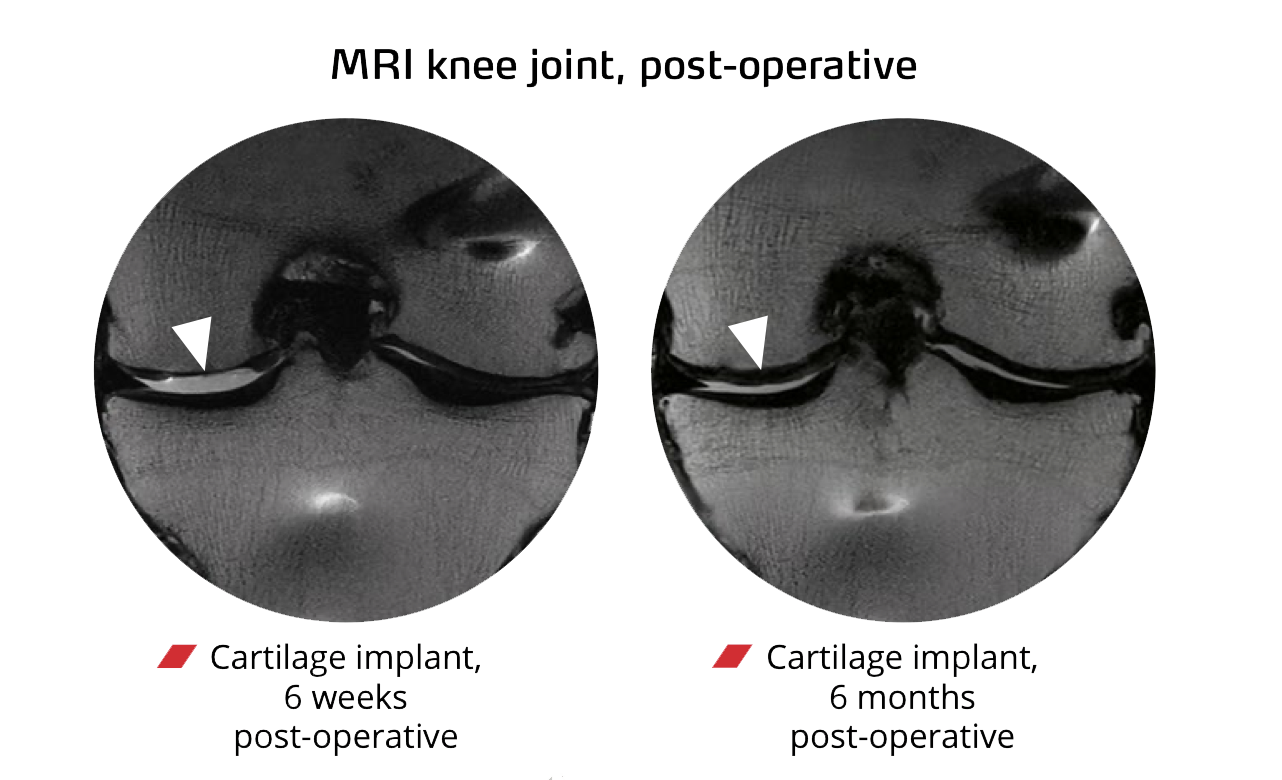

- MRI (MOCART scores): 70–87, indicating consistent, high-quality cartilage repair

Studies show +30 IKDC in knees, +33 Harris Hip Score in hips, and improved ankle mobility measures. MRI (MOCART) typically reports 70–87, indicating high-quality cartilage regeneration. >19,000 cases worldwide support safety and dependable restoration of everyday function.